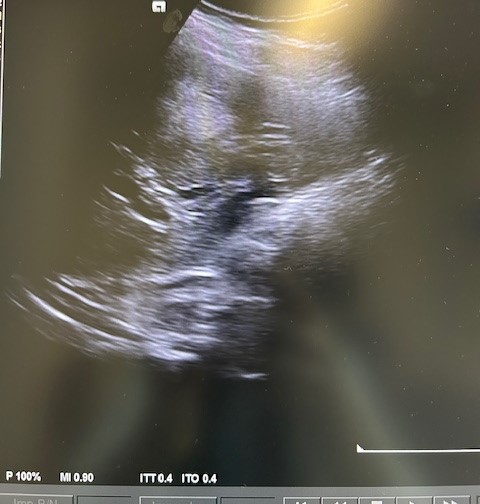

Descripción de los hallazgos ecográficos y las imágenes más relevantes para la resolución del caso

En la ecografía podemos apreciar hepatomegalia > 16 cm con múltiples imágenes en su interior hiperecogénicas sugestivas de LOE. No otros hallazgos a destacar.

El paciente fue valorado en Consultas Externas confirmando el diagnóstico. Se realiza ecografía abdominal con hallazgos de múltiples nódulos hepáticos de entre 12-35mm. En la colonoscopia, neoplasia circunferencial con aumento de consistencia, áreas ulceradas y necrosis, con estenosis incompleta, siendo compatible con adenocarcinoma de sigma.